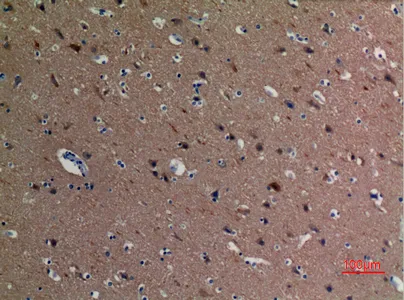

HSP90β (phospho Ser254) Rabbit Polyclonal Antibody

Cat: APRab04808